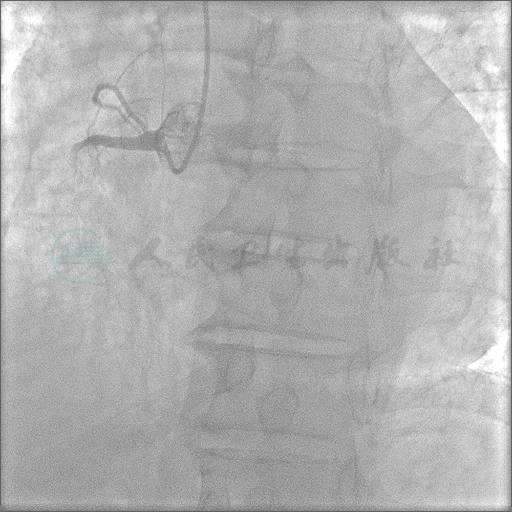

冠状动脉造影结果

经右桡动脉径路,6F鞘管,造影示RCA近段100%闭塞(图1),LM正常,LAD近段临界病变,LCX轻度病变,LAD-RCA侧支形成(图2、图3)

图1 左前斜位右冠状动脉造影